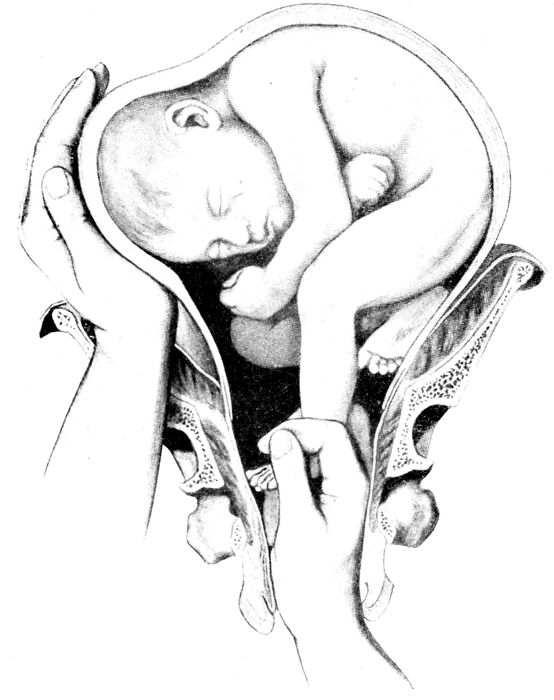

Extraction of the breech |

170 |

| |

| 64. |

Breech delivery. Extraction of the trunk |

171 |

| |

| 65. |

Breech delivery. Delivering the shoulder |

172 |

| |

| 66. |

The delivery of the after-coming head by the Smellie-Veit maneuver |

172 |